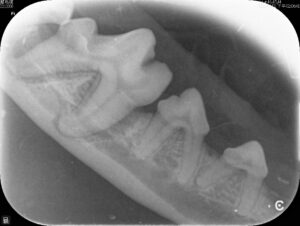

牙周治療到底在幹嘛? 不就是去動物醫院洗牙嗎?–新莊 布納動物醫院 小動物牙科 謝旻儒醫師